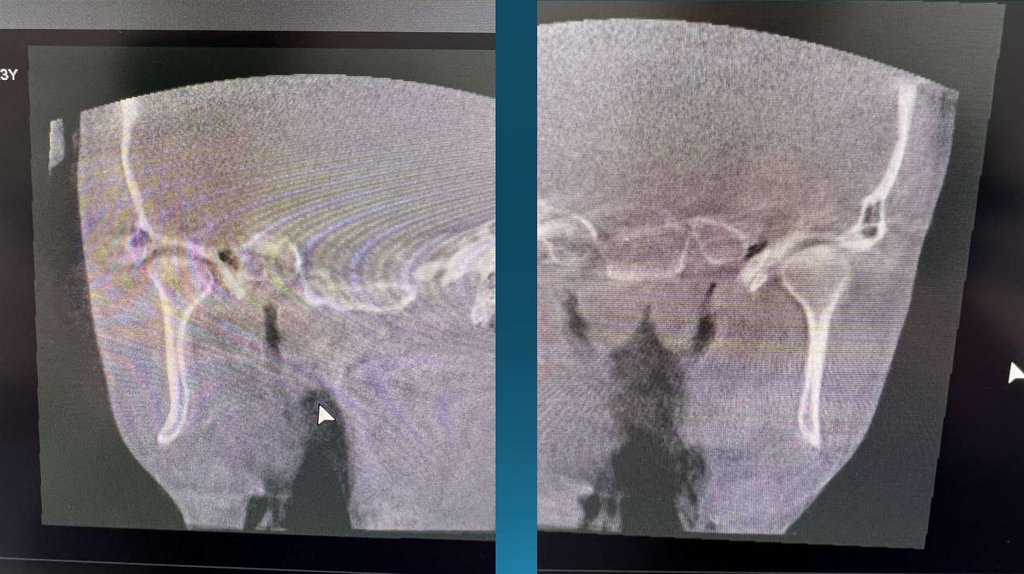

На клкт сильнейшая

компрессия биламинарной

зоны